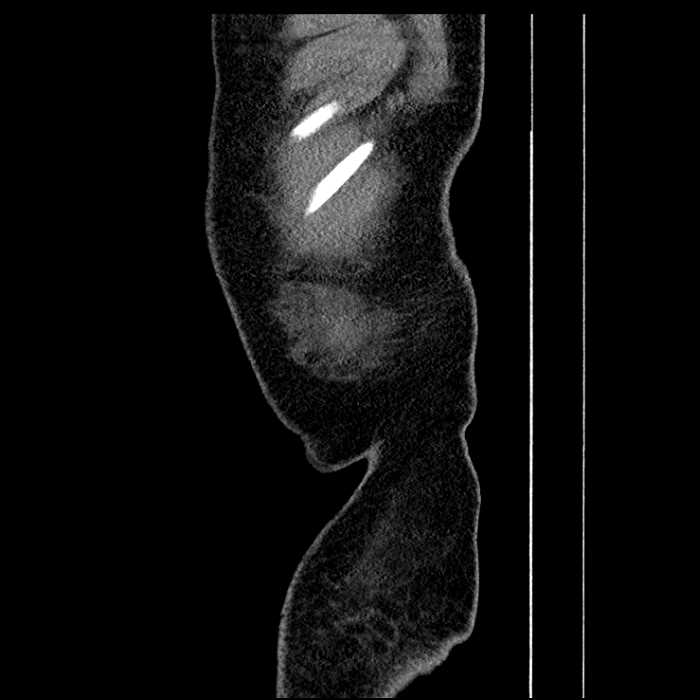

• Mild mural thickening of a segment of the sigmoid colon with adjacent fat stranding and a 1.5 cm fluid and gas collection along the tip of an inflamed diverticulum

• Loss of the normal fat plane between this collection and adjacent loops of small bowel, which demonstrate mural thickening

Acute sigmoid diverticulitis complicated by a small contained perforation and a large abscess in the right hepatic lobe. Additional small subcapsular abscesses along the anterior margin of the left hepatic lobe.

Additionally, loss of the normal fat plane between the peridiverticular collection and adjacent thickened loops of small bowel raises the potential for an enterocolonic fistula.

Hepatic abscess showing the double target sign with low density internally surrounded by a thin inner enhancing rim (red arrow) and ill-defined outer low density rim (yellow arrow). Blue arrow indicates an internal septation. Red arrows: additional smaller subcapsular abscesses. Red arrow: focal contained perforation associated with diverticulitis.